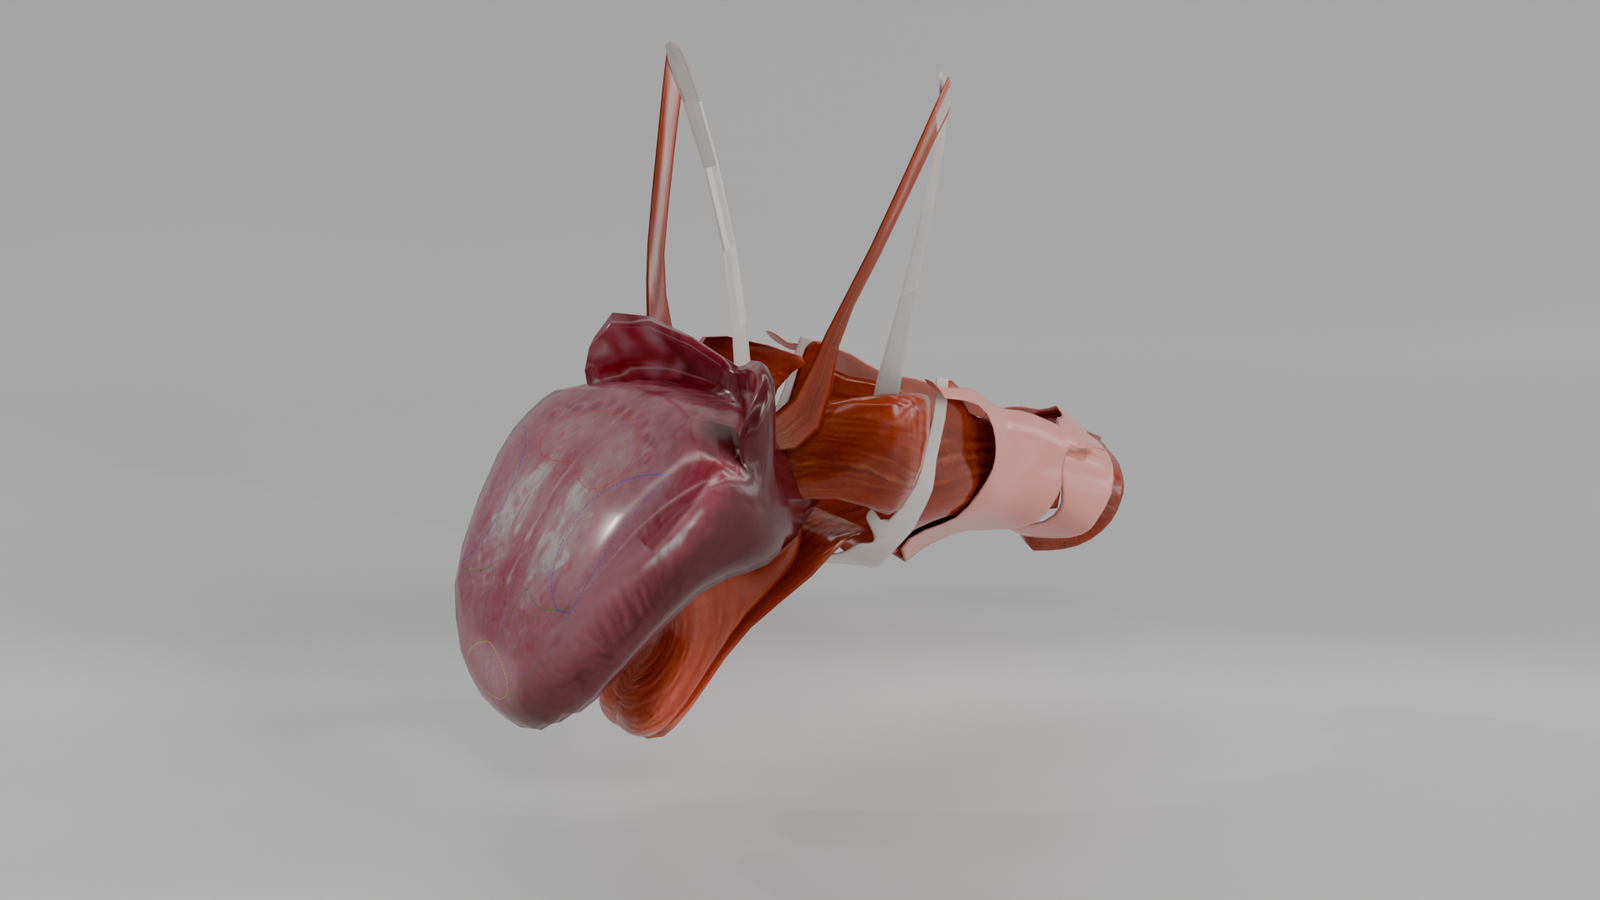

Cráneo Humano

Modelo 3D educativo